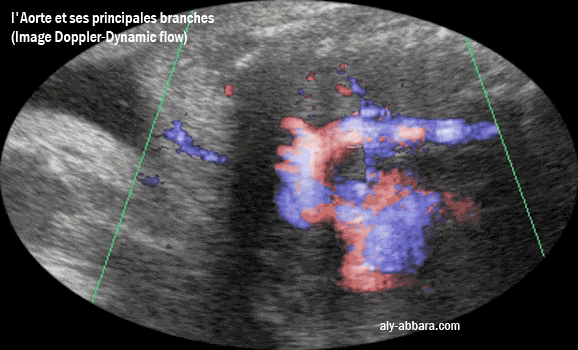

L'aspect échographique associé au Doppler-Dynamic-Flow de l'aorte ftale

avec ses portions et principales branches

Les branches artérielles naissant de la crosse de l'aorte : le tronc artériel brachio-céphalique,

puis l'artère carotide primaire gauche et enfin artère sous-clavière gauche